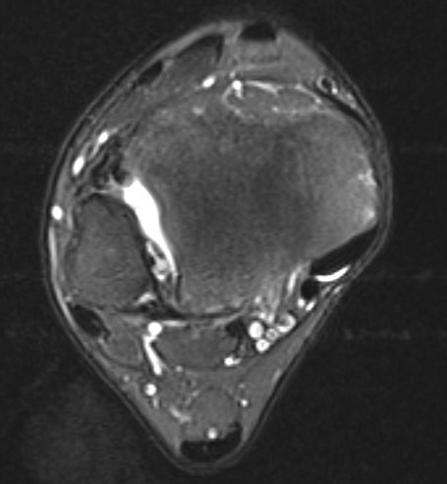

MRI

Tear of AITFL / intact PITFL

Tear of AITFL, intact PITFL, and syndesmotic injury with external rotation of the fibula

Tear of AITFL & PITFL with syndesmotic widening